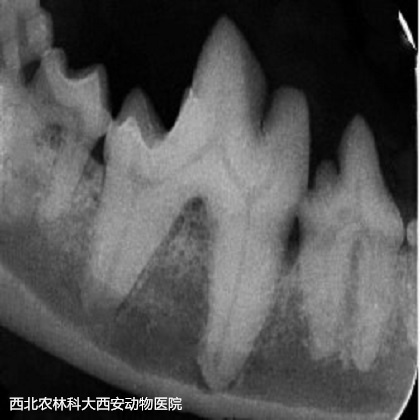

術(shù)前準(zhǔn)備:彈簧開口器撐開口腔,咽部填塞一塊紗布。檢查口腔,可見大量牙結(jié)石見(圖1)。超聲波潔牙術(shù):使用超聲波潔牙器將牙齒的齦上和齦下表面的牙結(jié)石和牙菌斑去除見(圖2)。在潔牙期間發(fā)現(xiàn)其上、下多個(gè)切齒均有松動(dòng),進(jìn)行牙科X線檢查見(圖3),并將上、下切齒各拔掉5顆。108號(hào)齒見(圖4)先前拍片提示存在口鼻瘺,采用注射器噴注可見口腔與鼻腔(右側(cè))連通,使用裂鉆將牙根分開見(圖5),并將牙根分別拔除,口鼻瘺內(nèi)存在多量粘稠惡臭物見(圖6),徹底沖洗口鼻瘺處。牙科手術(shù)刀于上黏膜瓣切出一U形切口,用縫線將黏膜瓣和腭側(cè)黏膜對(duì)合后結(jié)節(jié)縫合見(圖7)。最后,清理口腔去除咽部填塞的紗布?jí)K。術(shù)后通過靜脈輸液給予抗生素和止血藥物。術(shù)后一周每天沖洗口腔兩次,涂抹凝膠四次。一周后回訪恢復(fù)較好,口臭明顯改善,未再出現(xiàn)打噴嚏和流鼻。

圖三